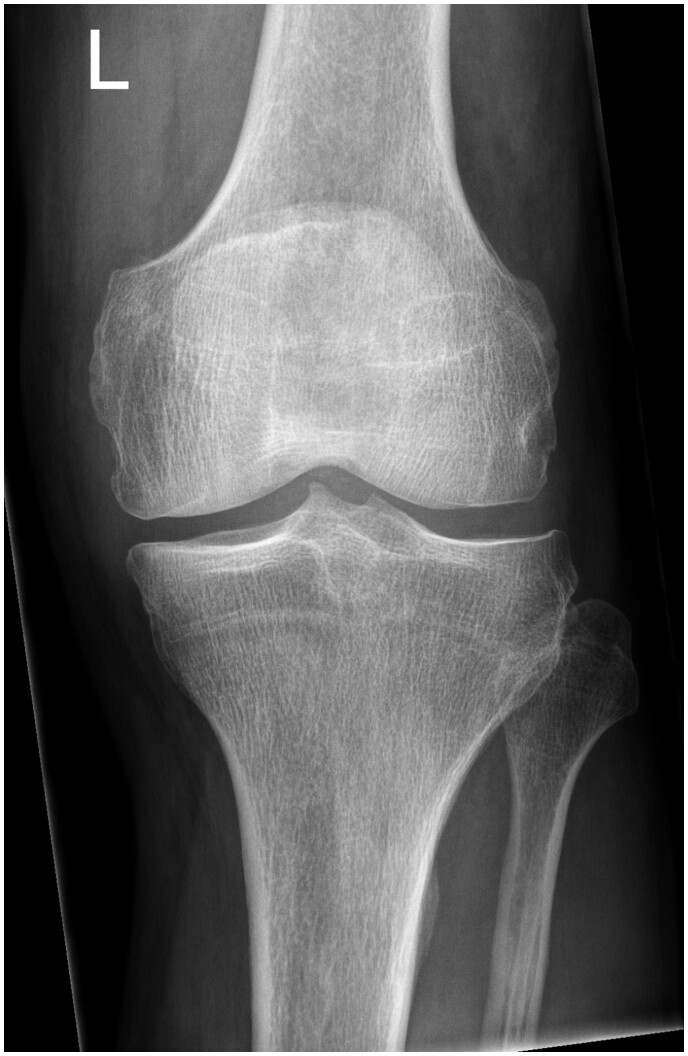

We present the radiological findings in the case of a failed unicompartmental knee arthroplasty (UKA). Although uncommon, these features are highly specific for implant failure and are an indication to consider revision. The aim of this case report is to highlight these characteristic appearances across multiple imaging modalities to both surgeons and radiologists should they encounter this in their practise.

Abstract Image